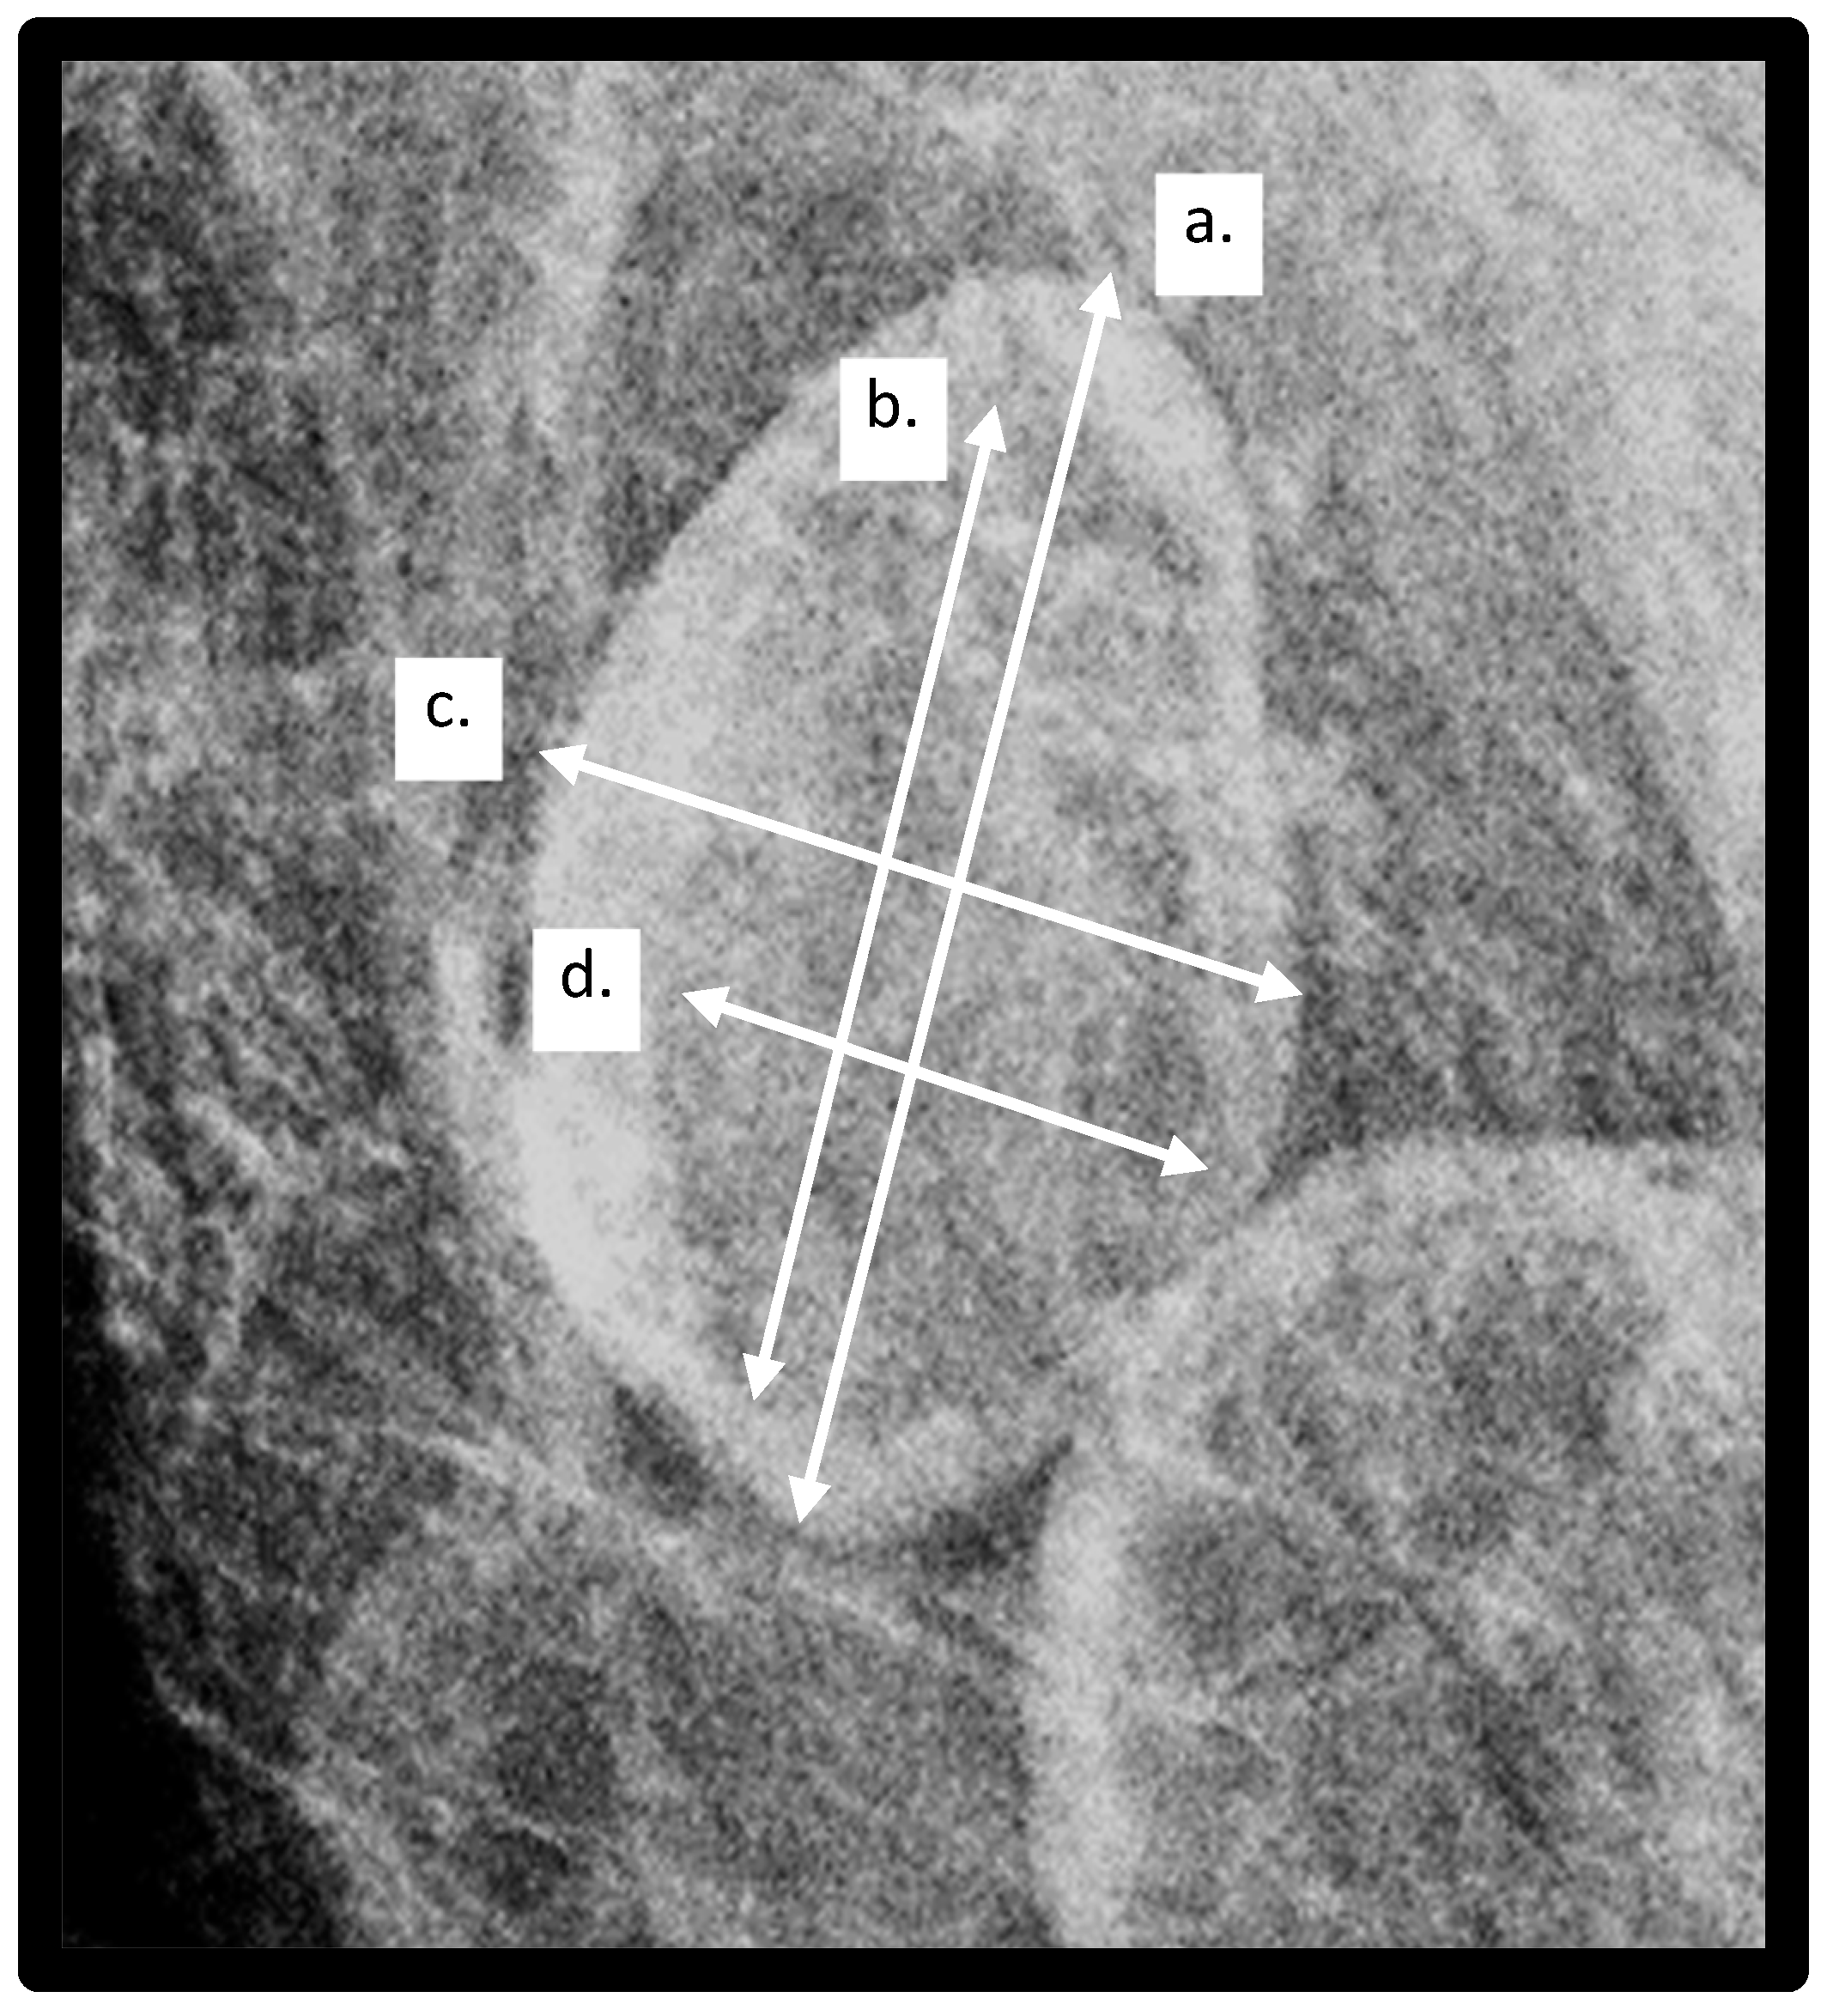

Image Analysis: Using Selenia and Dimensions Hologic units (Hologic Incorporated, Bedford, MA, USA), two-dimensional full-field digital mammograms were obtained, and images were reviewed on Barco 3-megapixel MDCG-3221 monitors (Kortrijk, Belgium) with Philips PACS v3.6 (Philips Healthcare, Best, The Netherlands). A breast radiologist (RDA) and senior radiology resident (KP), who were blinded to the patients’ clinical histories, reviewed each mammogram for the presence of visible lymph nodes. The single largest LN within either the right or left MLO view was chosen as the index node and was included for analysis if at least 80% of the LN was visible on the mammogram. The largest lymph node was selected as the index node for analysis based on prior work showing that the largest lymph node is correlated with obesity and adverse health outcomes [16]. Measurements obtained of the index lymph node included total LN length and width and hilar length and width. The LN cortex was defined as the peripheral radio-dense portion of the LN, and the LN hilum was measured as the radiolucent central area. Examples of lymph node and hilar measurements are demonstrated in Figure 3.

Figure 3.

Lymph node (LN) measurements obtained: a—LN length, b—Hilar length, c—LN width, d—hilar width.